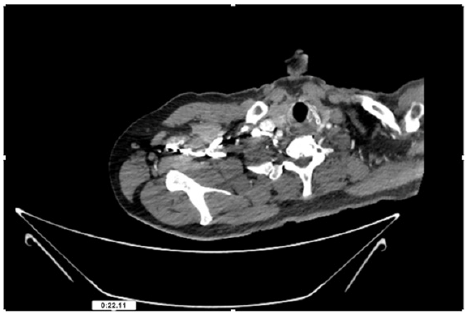

55-years-old chronic smoker had acute, severe pain in the right upper limb for one week; it was cold upto mid arm with skin discoloration. He also noticed numbness and weakness of movement of elbow joint. He underwent below elbow amputation in February 2023 for acute ischemia of left upper limb. He was a current chronic smoker; 15 pack year. General condition was weak; temperature was normal; blood pressure was 100/60mmHg; heart rate was 92/minutes with sinus rhythm; SpO2 was 97% on air; heart was normal. In lower extremities, all peripheral pulses were intact. Local Examination of right upper limb revealed as follows: tenderness; coldness; discoloration; decreased motor function and sensory modalities. Axillary, brachial and radial pulses were not palpable. Hand-held Doppler failed to detect any signal in arterial system; therefore, we arranged for emergency embolectomy. complete occlusion of right upper limb arterial system Full blood count showed high hemoglobin (14.6gm%); normal total WBC and platelet count. Coagulation profile was normal. Parenteral unfractionated heparin, antibiotics, tramadol, proton-pump inhibitors, anti-platelets and HMG CoA reductase inhibitors were given. Doppler ultrasound demonstrated complete occlusion of right upper limb arterial system. CT Angiogram illustrated occlusion of subclavian artery downwards on both sides. Figures 1-14 shows complete occlusion of right subclavian artery without collaterals. On Day ‘2’ of admission, the patient passed black tarry stool for 3 times. However, the vital signs were stable; blood pressure was 100/60mmHg; heart rate was 92/min; SpO2 was 97% on air; the abdomen was soft and not tender. Above elbow amputation was done on Day ‘2’ of admission. Intra-operative findings were as follows: (1) no active bleeding at brachial artery; (2) thrombosis along brachial artery; (3) muscle color and consistency were not healthy.

Figure 4: CT Angiogram at neck showing normal brachio-cephalic trunk, common carotid artery, and narrow right subclavian artery.

Figure 5: CT Angiogram at neck showing normal brachio-cephalic trunk, common carotid artery, and narrow right subclavian artery.

Figure 6: CT Angiogram at neck showing brachio-cephalic trunk, common carotid artery and narrow right subclavian artery.

Figure 7: CT Angiogram at neck showing brachio-cephalic trunk, common carotid artery and narrow right subclavian artery.